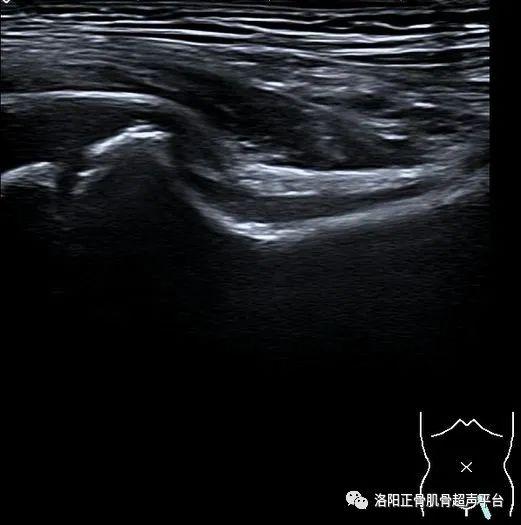

病例分享小儿髋关节滑膜嵌顿症

图片尺寸521x525

图片尺寸756x696